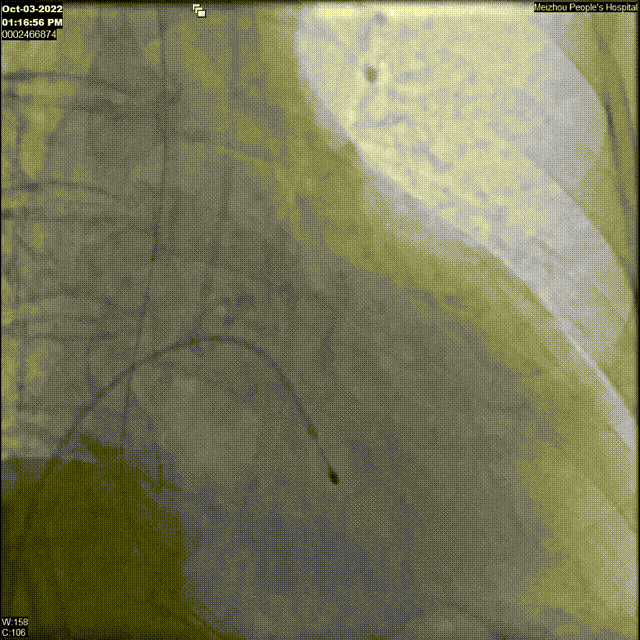

3、主动脉根部影像

主动脉根部造影